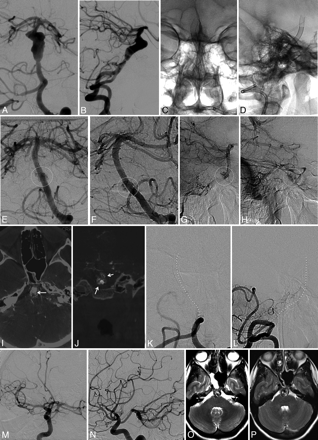

An adult female patient with a family history of aneurysmal subarachnoid hemorrhage presented with a history of progressively worsening intractable headache. An initial evaluation for meningitis was negative, and ultimately cross-sectional brain imaging was performed. CT, CTA, and MR imaging demonstrated a partially thrombosed very large fusiform aneurysm circumferentially involving a 22-mm segment of the basilar trunk (Fig 1).

Subtracted PA (A) and lateral (B) pretreatment angiographic projections demonstrate a fusiform aneurysm with incorporation of a 20-mm segment of the midbasilar trunk. The trajectory of the distal basilar artery appears displaced posteriorly and to the right with respect to the trajectory of the proximal basilar trunk. Native PA (C) and lateral (D) projections following treatment demonstrate a 4-PED construct bridging the aneurysmal segment of the basilar trunk. Subtracted PA (E) and slightly oblique (F) projections from 3- (E) and 12-month (F) follow-up angiograms demonstrate an irregularly marginated neck entry remnant along the posterior aspect of the midconstruct, demarcated by dotted circles. Subtracted capillary (G) and late venous (H) phase lateral images from the 12-month follow-up study demonstrate the margins of the residual pocket, demarcated by dotted circles, to be somewhat irregular, with an appearance suggesting gradual penetration into the thrombosed portion of the aneurysm during the later phases of the angiogram. Axial (I) and coronal (J) reformations of source data derived from a cone-beam CTA (DynaCT) following an intra-arterial contrast injection (arrows) demonstrate transit of contrast material through the PED construct with irregular penetration into the intra-aneurysmal thrombus mass. In addition, the overall size of the aneurysm–intra-aneurysmal thrombus mass has not regressed in comparison with original cross-sectional imaging studies obtained before treatment. Subtracted PA (K) and lateral (L) images from an angiogram obtained 10 days after discontinuation of clopidogrel demonstrate complete occlusion of the PED construct. The normal trajectory of the reconstructed basilar artery is demarcated by a dotted line on each image. Subtracted oblique (M) and lateral (N) images demonstrate a large patent right posterior communicating artery providing perfusion of the distal basilar artery and basilar apex. Long TR-weighted axial imagings performed before (O) and 13 months after (P) treatment confirm that the size of the aneurysm-thrombus mass complex had not regressed to any extent after the initial PED reconstruction, suggesting continued viability of the aneurysm despite PED treatment and near-complete thrombosis on angiography during the next 12 months.

An adult male patient presented with progressive headache, double vision, and hyperreflexia. Cross-sectional imaging demonstrated a very large fusiform aneurysm circumferentially involving a 25-mm segment of the proximal basilar trunk with incorporation of the vertebrobasilar junction (Fig 2).

Subtracted PA (A) and oblique (B) images demonstrate a fusiform aneurysm circumferentially incorporating a 25-mm segment of the basilar artery, extending from just beyond the origin of the AICAs proximally to involve the vertebrobasilar junction. C, Native oblique projection following reconstruction of the vertebrobasilar junction with a PED construct extending from the distal right vertebral artery to the distal basilar artery and coil deconstruction of the distal left vertebral artery. Additional markers within the aneurysm fundus demarcate the ends of 2 Solitaire stents, which had been deployed during a prior (unsuccessful) attempt at treatment. Subtracted angiographic images during the early (D) and mid (E) arterial phases as well as the venous (F) phase from an 11-month follow-up angiogram demonstrate residual filling of the aneurysm via a neck-entry remnant adjacent to the left AICA origin. Later phase imaging demonstrates penetration of contrast material (arrows) deep into the intra-aneurysmal thrombus mass. Subtracted PA image (G) from a 12-month follow-up angiogram demonstrates complete occlusion of the PED construct. H, The normal trajectory of the reconstructed distal right vertebral artery and basilar trunk is demarcated in the adjacent figure by a dotted white line. Subtracted PA angiographic image obtained during the emergent revascularization of the PED construct demonstrates restoration of the patency of the construct with a small amount of residual thrombus material within the basilar apex and proximal posterior cerebral arteries.